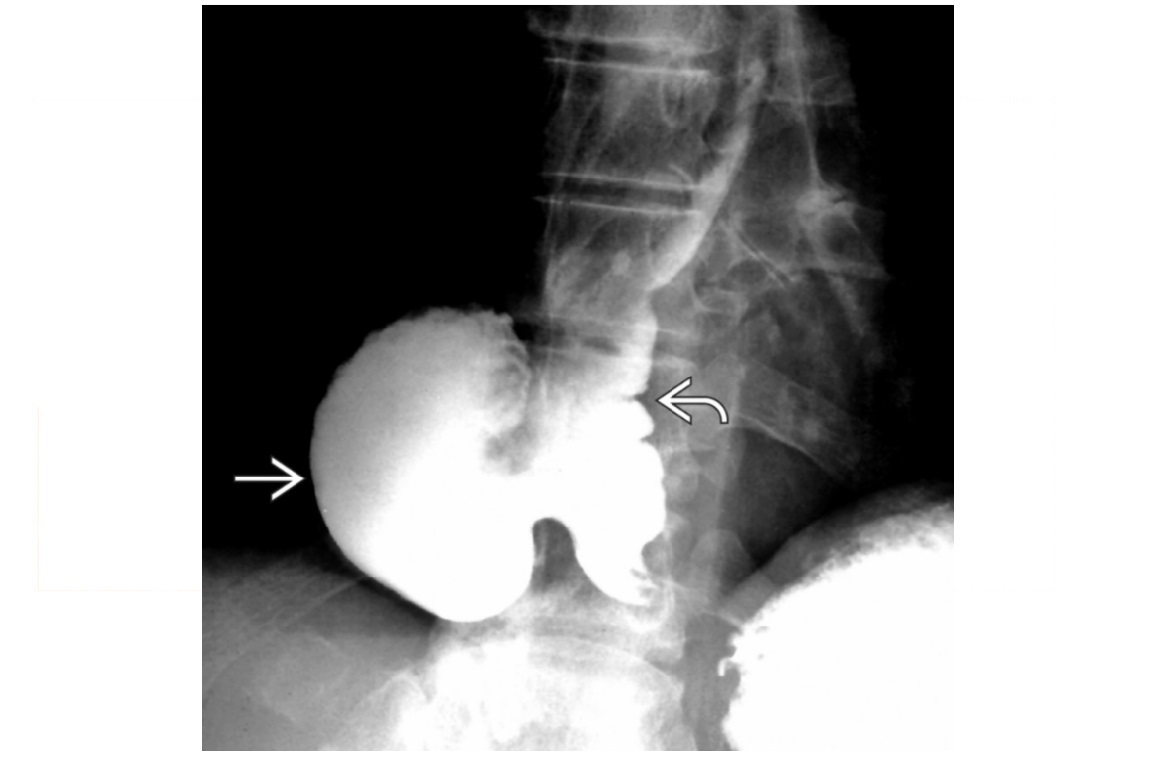

Sigmoid Vovulus Inverted U shape Ahaustra Coffee bean - cleft is double thickenss of opposed bowel loops Directed toward right upper quadrant (RUQ) or left upper quadrant (LUQ); Look for - Gas in proximal small bowel and colon Abscence of air in rectum Tend to be older patients Mx with rectal decompression

Caecal voluvulus Dilated, air-filled left upper quadrant or abdominal midline Haustra Single, long air-fluid level within cecum (upright or decubitus film) Moderately distended small bowel, little gas in distal colon Markedly dilated cecum that appears upside down and backward with ileocecal valve directed laterally